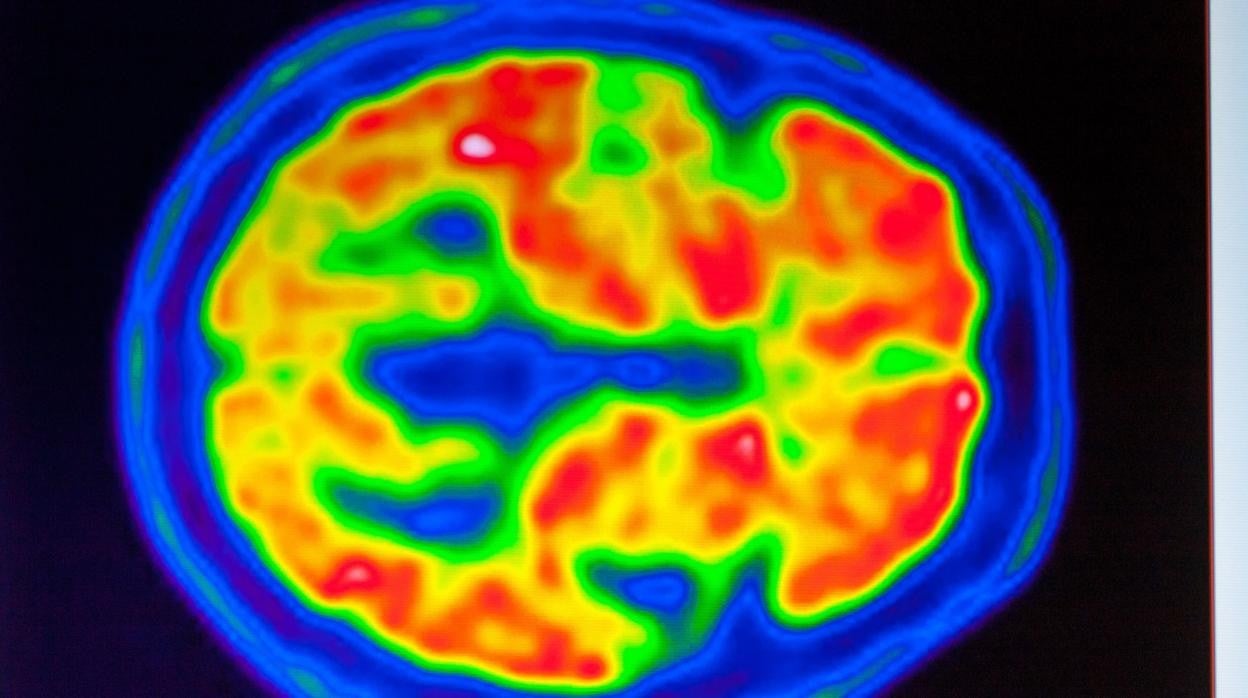

Según la compañía que lo fabrica, Biogen , el fármaco, un anticuerpo monoclonal, a dosis altas es capaz de eliminar las placas de la proteína amiloide del cerebro que se han acumulado durante años. Esas placas son características de las personas con alzhéimer, ya que impiden la conexión correcta entre las neuronas y provocan su degeneración.

Si bien el amiloide se considera un biomarcador de alzhéimer porque su acumulación en el cerebro es clave, hay muy poca evidencia científica de que su reducción puede ayudar a los pacientes al aliviar sus problemas de memoria y pensamiento.

De hecho, durante más de dos décadas, los ensayos clínicos con otros fármacos reductores de amiloide no han podido ofrecer pruebas de que realmente ralentizaran el deterioro cognitivo.